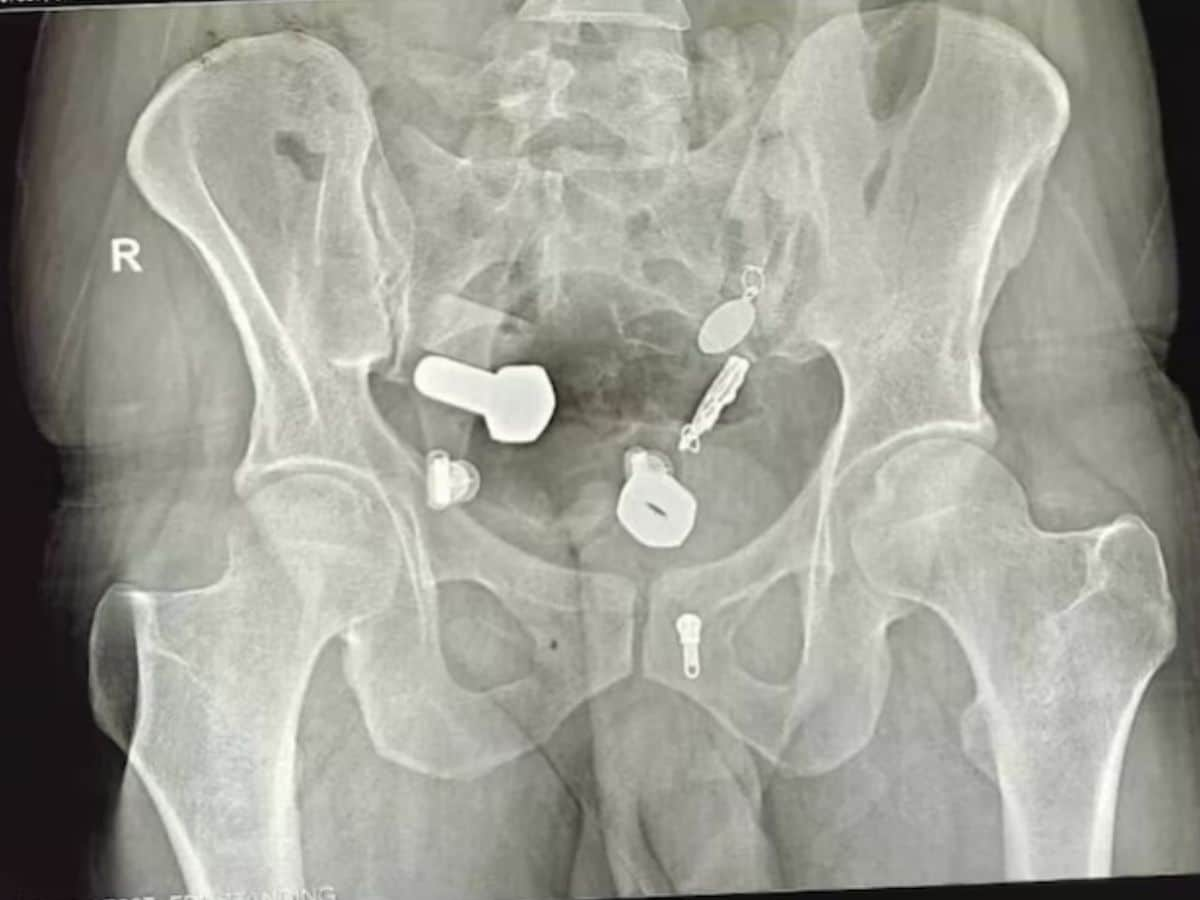

डॉक्टरांनी त्याच्या टेस्ट केल्या. रिपोर्टमध्ये त्यांना जे दिसलं त्यावर त्यांचाही विश्वास बसेना. रुग्णाच्या मोठ्या आतड्यात अनेक नट, बोल्ट आणि लोखंडाचे छोटे तुकडे होते. तसंच घड्याळही अडकलं होतं.

त्यानंतर सर्जनच्या टीमने हे आव्हानात्मक ऑपरेशन यशस्वीरित्या पार पाडलं, जे सुमारे तीन तास चाललं. डॉक्टरांनी पोटात एक छोटासा चीरा टाकला आणि सर्व वस्तू काढल्या. हॉस्पिटलमधून प्रसिद्ध झालेल्या धक्कादायक फुटेजमध्ये डॉक्टर रुग्णाच्या पोटातून घड्याळ आणि इतर धातूच्या वस्तू एक-एक करून बाहेर काढताना स्पष्टपणे दिसत आहेत.